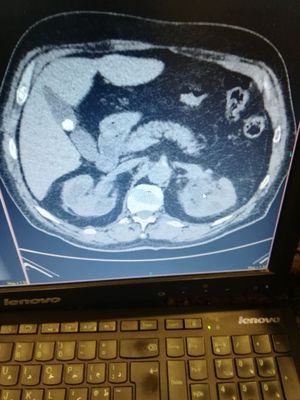

Any comment about the finding plz?? The ot pressent with flank pain and he has UTI.

Surgery

Ct

Abdominal